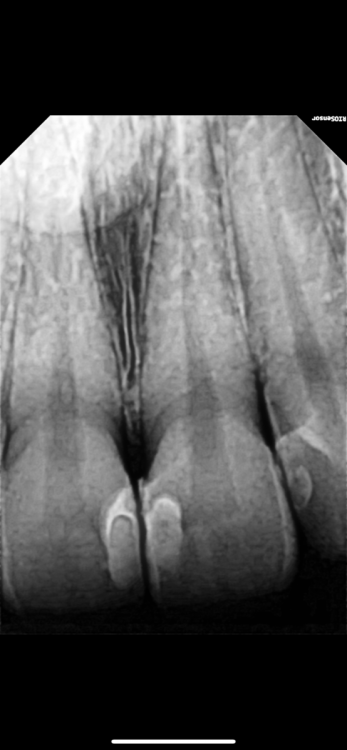

Мари12345 Опубликовано 8 февраля, 2024 Поделиться Опубликовано 8 февраля, 2024 Добрый день! Помогите, пожалуйста, разобраться, хорошо ли установлена пломба на двух единичках? Недавно её поставила, вчера сделала снимок и вижу, что у пломбы неровные, волнистые края, а такое на пломбе есть контрастные полоски. Подскажите, это нормально или её нужно менять ? Заранее спасибо Ссылка на комментарий

red_butler Опубликовано 8 февраля, 2024 Поделиться Опубликовано 8 февраля, 2024 44 минуты назад, Мари12345 сказал: Подскажите, это нормально или её нужно менять ? Здравствуйте, менять не нужно, посетите своего врача и он сгладит края штрипсой. 1 Ссылка на комментарий